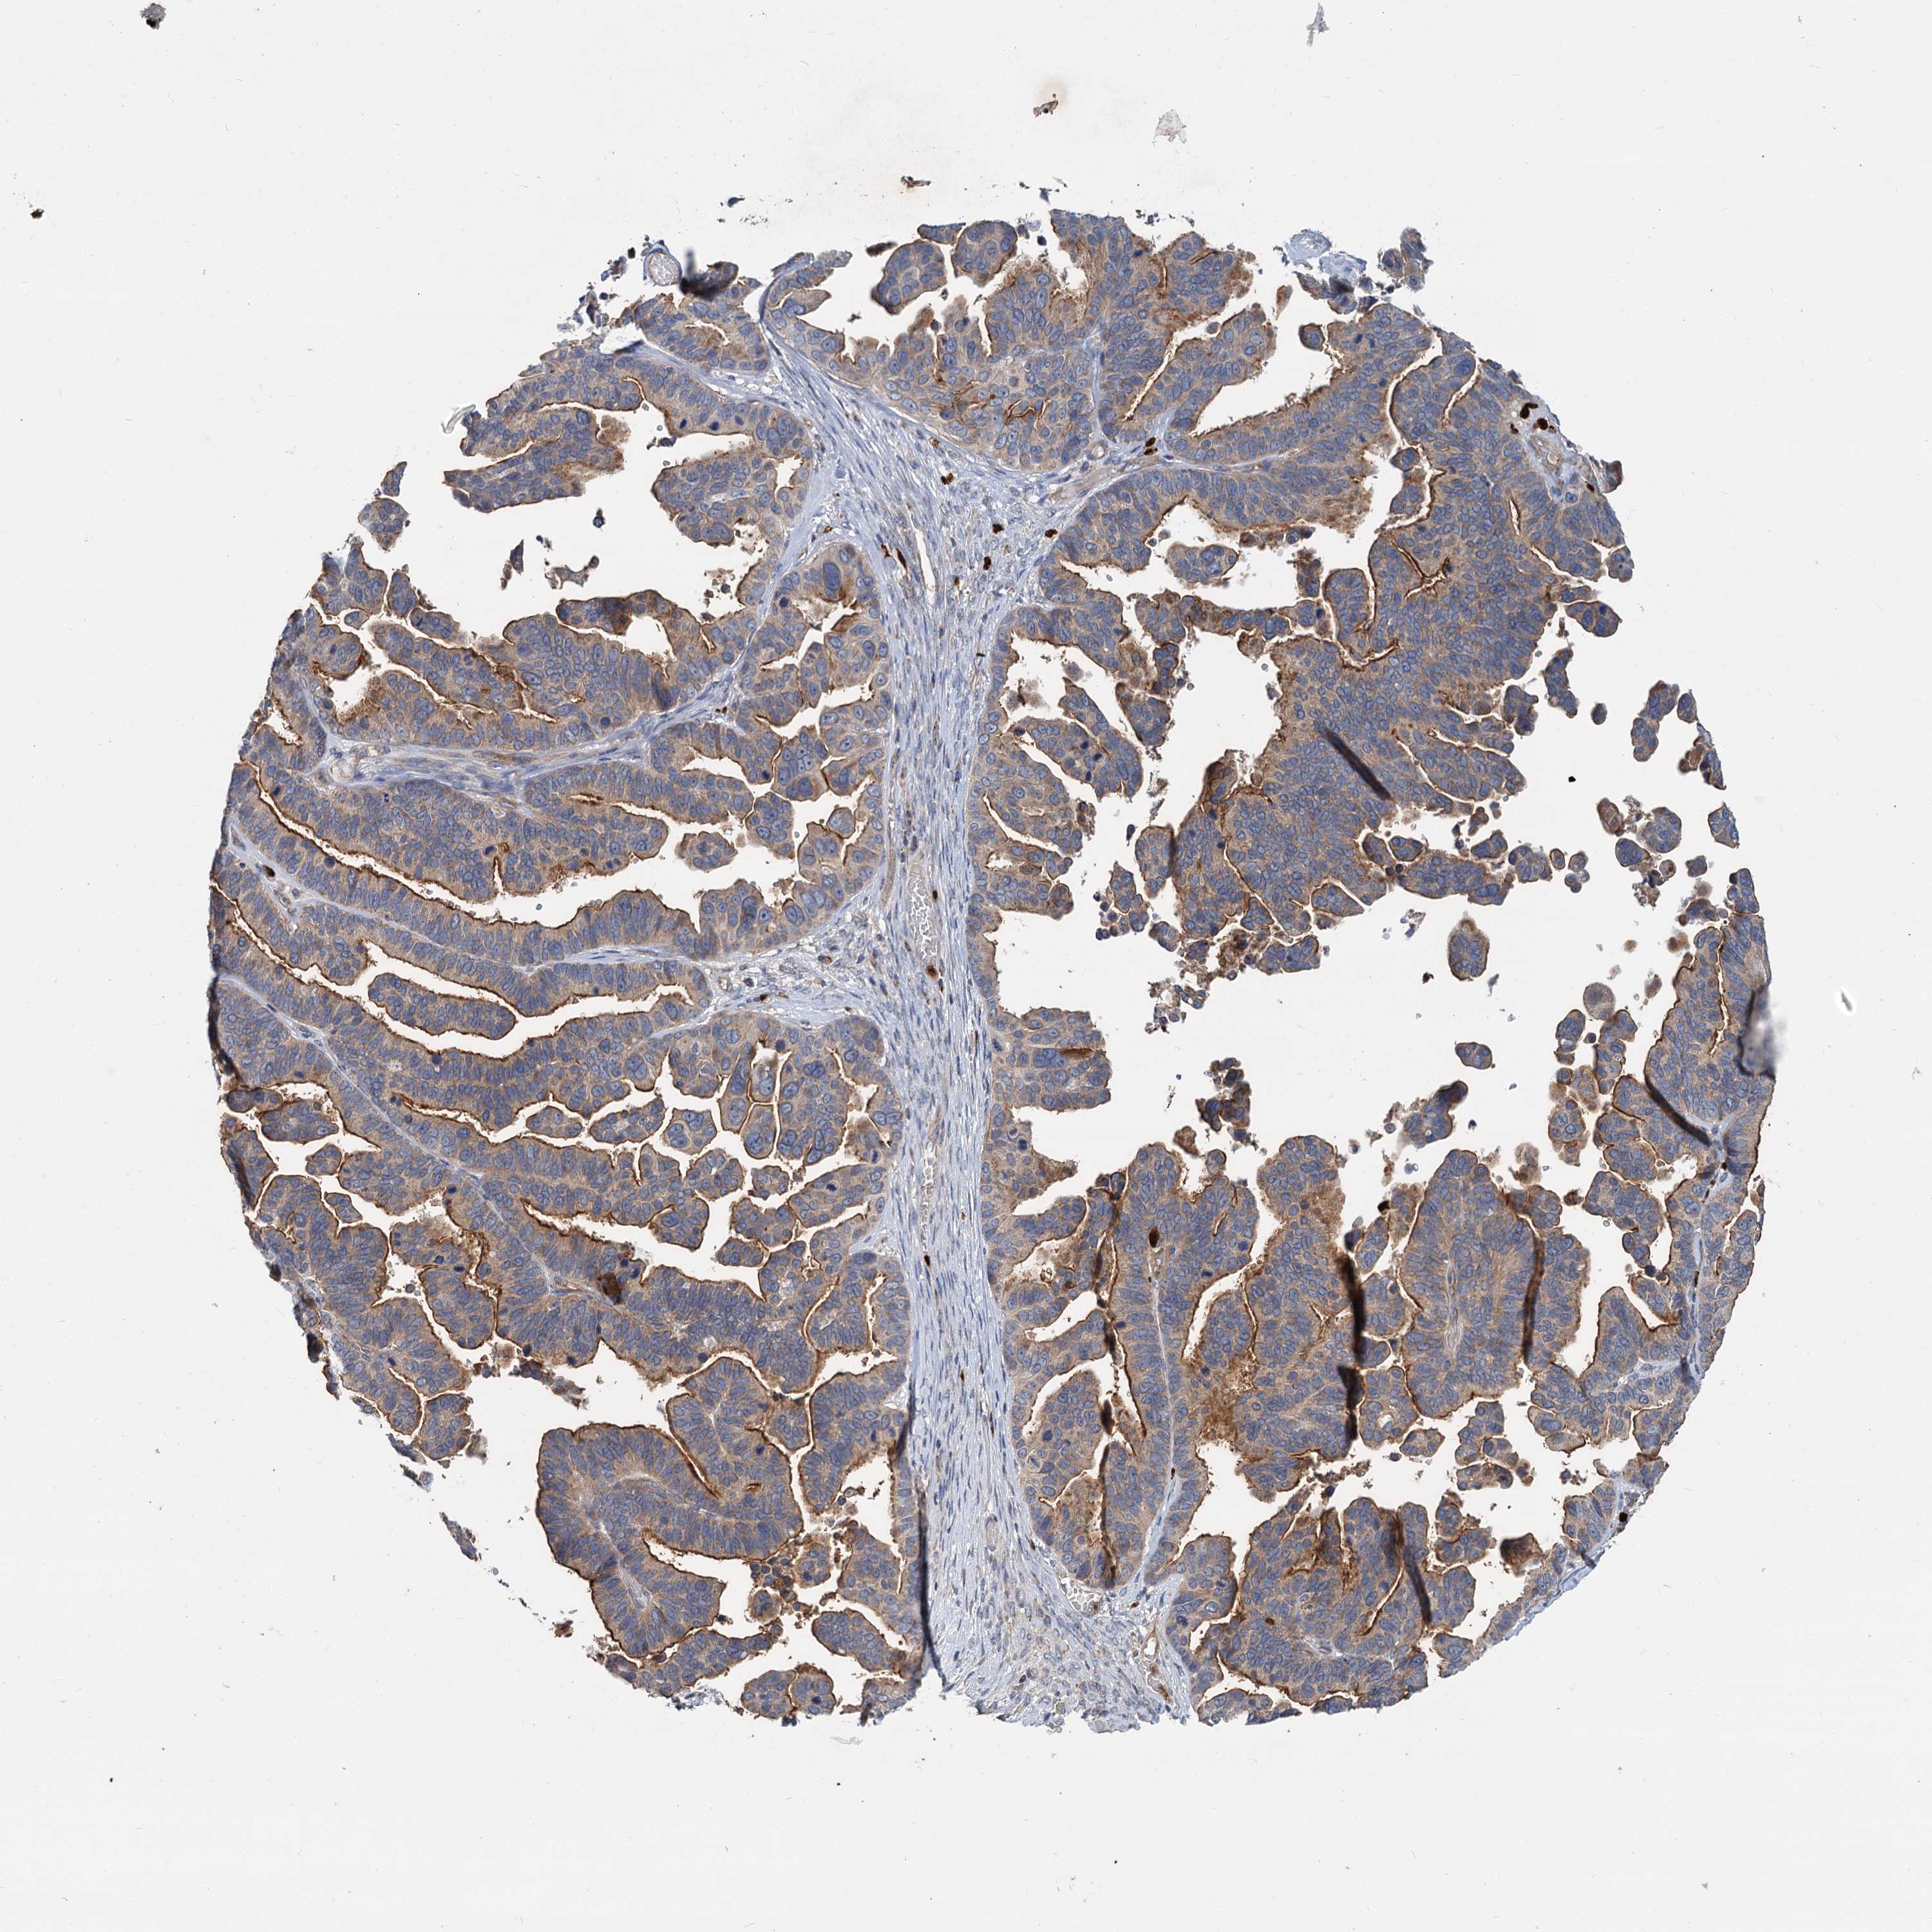

OVARIAN CANCER - Protein expressioni

A mouse-over function shows sample information and annotation data. Click on an image to view it in a full screen mode. Samples can be filtered based on level of antibody staining by selecting one or several of the following categories: high, medium, low and not detected. The assay and annotation is described here.

Note that samples used for immunohistochemistry by the Human Protein Atlas do not correspond to samples in the TCGA dataset.

Antibody stainingi

Antibody staining in the annotated cell types in the current human tissue is reported as not detected, low, medium, or high, based on conventional immunohistochemistry profiling in selected tissues. This score is based on the combination of the staining intensity and fraction of stained cells.

Each image is clickable and will lead to virtual microscopy that enables deeper exploration of all samples and also displays staining intensity scores, fraction scores and subcellular localization as well as patient and tissue information for each sample.

Antibody HPA039015

Antibody HPA039016

Carcinoma, endometroid